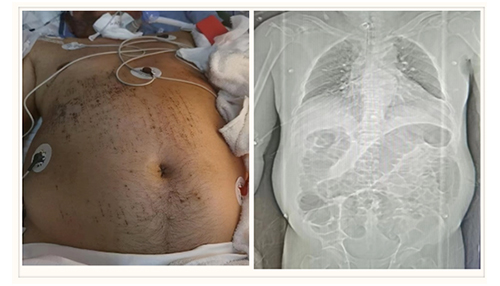

患者为60岁男性,不幸因车祸受伤,致双侧硬膜外、硬膜下血肿、脑挫裂伤、蛛网膜下腔出血、多发颅面骨骨折、肋骨骨折、左侧肱骨多发骨折、多发腰椎横突骨折以及骨盆骨折。患者伤后立即被送至当地某三甲医院就诊,因病情危重被收入重症医学科。治疗过程中患者出现了肠梗阻、双下肢静脉血栓、肺部感染、持续昏迷等情况,当地医院束手无策,转诊至我院东院创伤四科(创伤重症病房)。

转来时患者呈意识不清、躁动,气管切开,腹胀如鼓,肠鸣音消失,若不及时处理,患者很容易出现肠缺血、坏死、腹腔高压等情况,危及生命。同时患者有双下肢肌间静脉、腓静脉血栓,强化CT显示双下肺动脉部分分支栓塞,使得情况变得更加复杂。